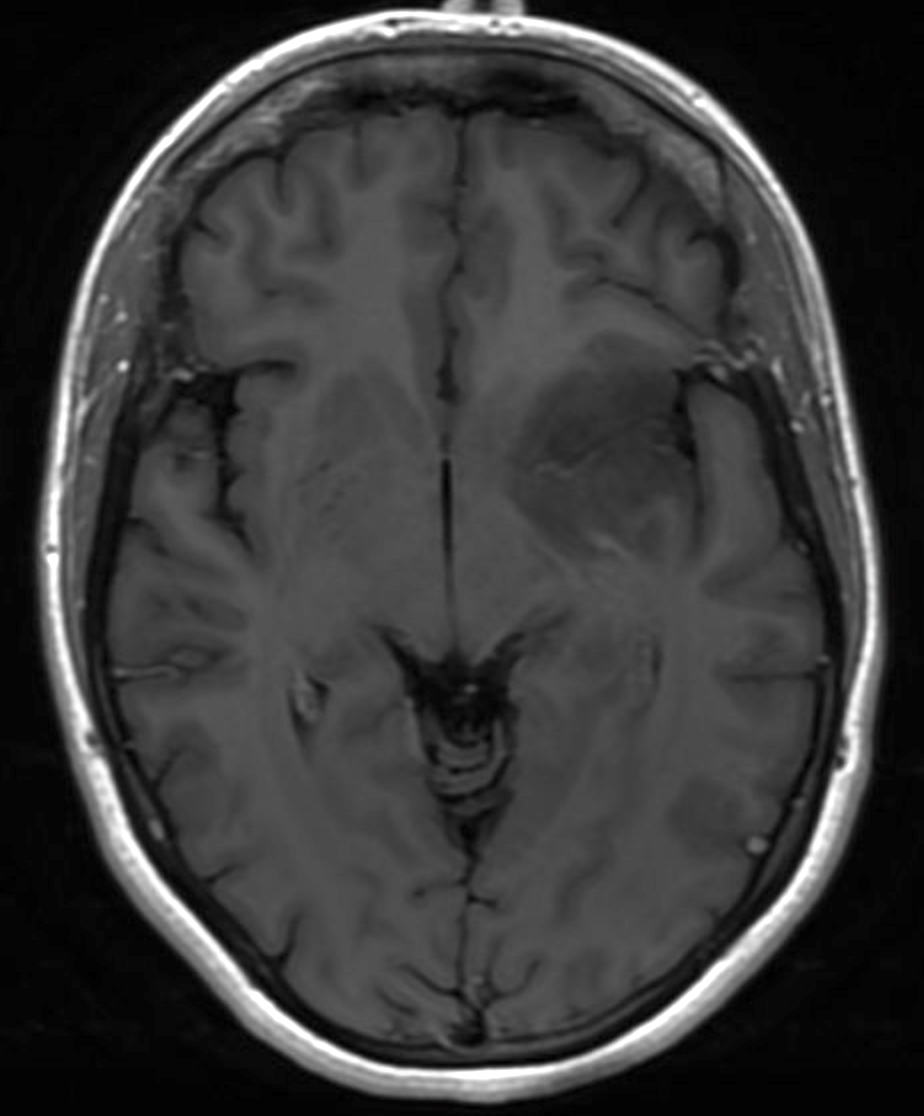

Radiology description

- Computed topography (CT):

- Mixed density (hypodense and isodense) located in cortex or subcortical white matter (Radiology 2017;284:316)

- High attenuation areas, likely from calcifications

- MRI:

- Heterogeneous on T1 and T2 weighted imaging

- Typically no diffusion restriction

- Poorly circumscribed borders (AJNR Am J Neuroradiol 2017;38:678)

- Cystic changes are relatively common (Radiology 2017;284:316)

- Contrast enhancement present in < 20% of WHO grade 2 tumors and > 70% of WHO grade 3 tumors (AJNR Am J Neuroradiol 2012;33:852, Eur J Cancer 2019;107:15)

- Elevated 2HG by magnetic resonance spectroscopy could serve as radiologic surrogate of IDH mutation status (Nat Med 2012;18:624)

Radiology images